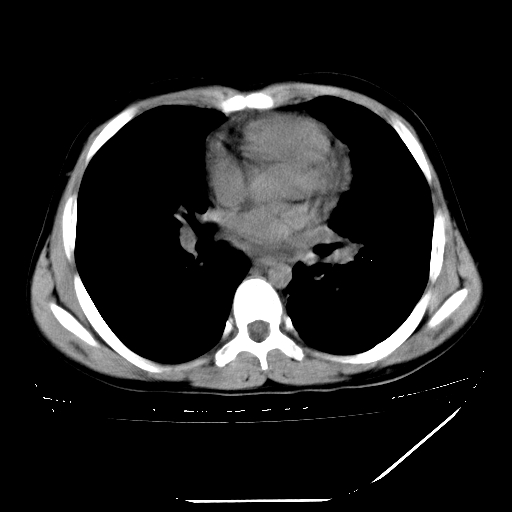

男,13岁,咳嗽、咳痰伴发热一周。

上纵隔课件多枚淋巴结,部分相互融合,左侧支气管壁增厚,肺纹理较右侧增粗,患者,男,13岁,

中上纵隔见多枚淋巴结肿大,部分相互融合成团片,左肺门增大,上叶支气管变窄,肺内多处斑片状 索条状及棉絮状致密影。临床“男,13岁,咳嗽、咳痰伴发热一周。”首先考虑:原发综合征!不除外淋巴瘤可能!

纵隔多发肿大淋巴结,部份有融合改变。双肺血管气管束增厚,以肺门为中心向外周散发,以左肺下叶为明显。考虑淋巴瘤可能性大。不除外原发综合征。

中上纵隔见多枚淋巴结肿大,部分相互融合成团片,左肺门增大,上叶支气管变窄,左肺支气管血管束增粗,可见磨玻璃样影。临床“男,13岁,咳嗽、咳痰伴发热一周。”首先考虑:淋巴瘤可能性大!